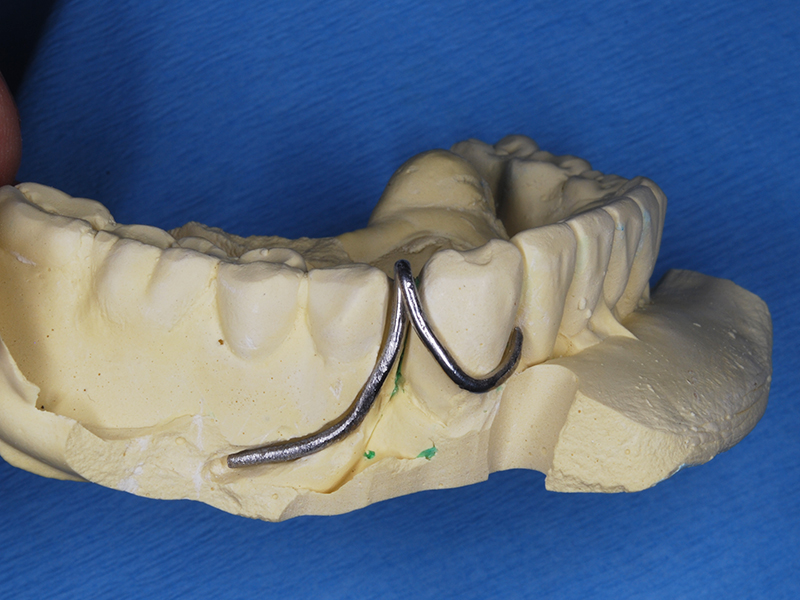

模型上で凹み部分にクラスプ新製

凹みの仮封鎖を取りクラスプ適合確認